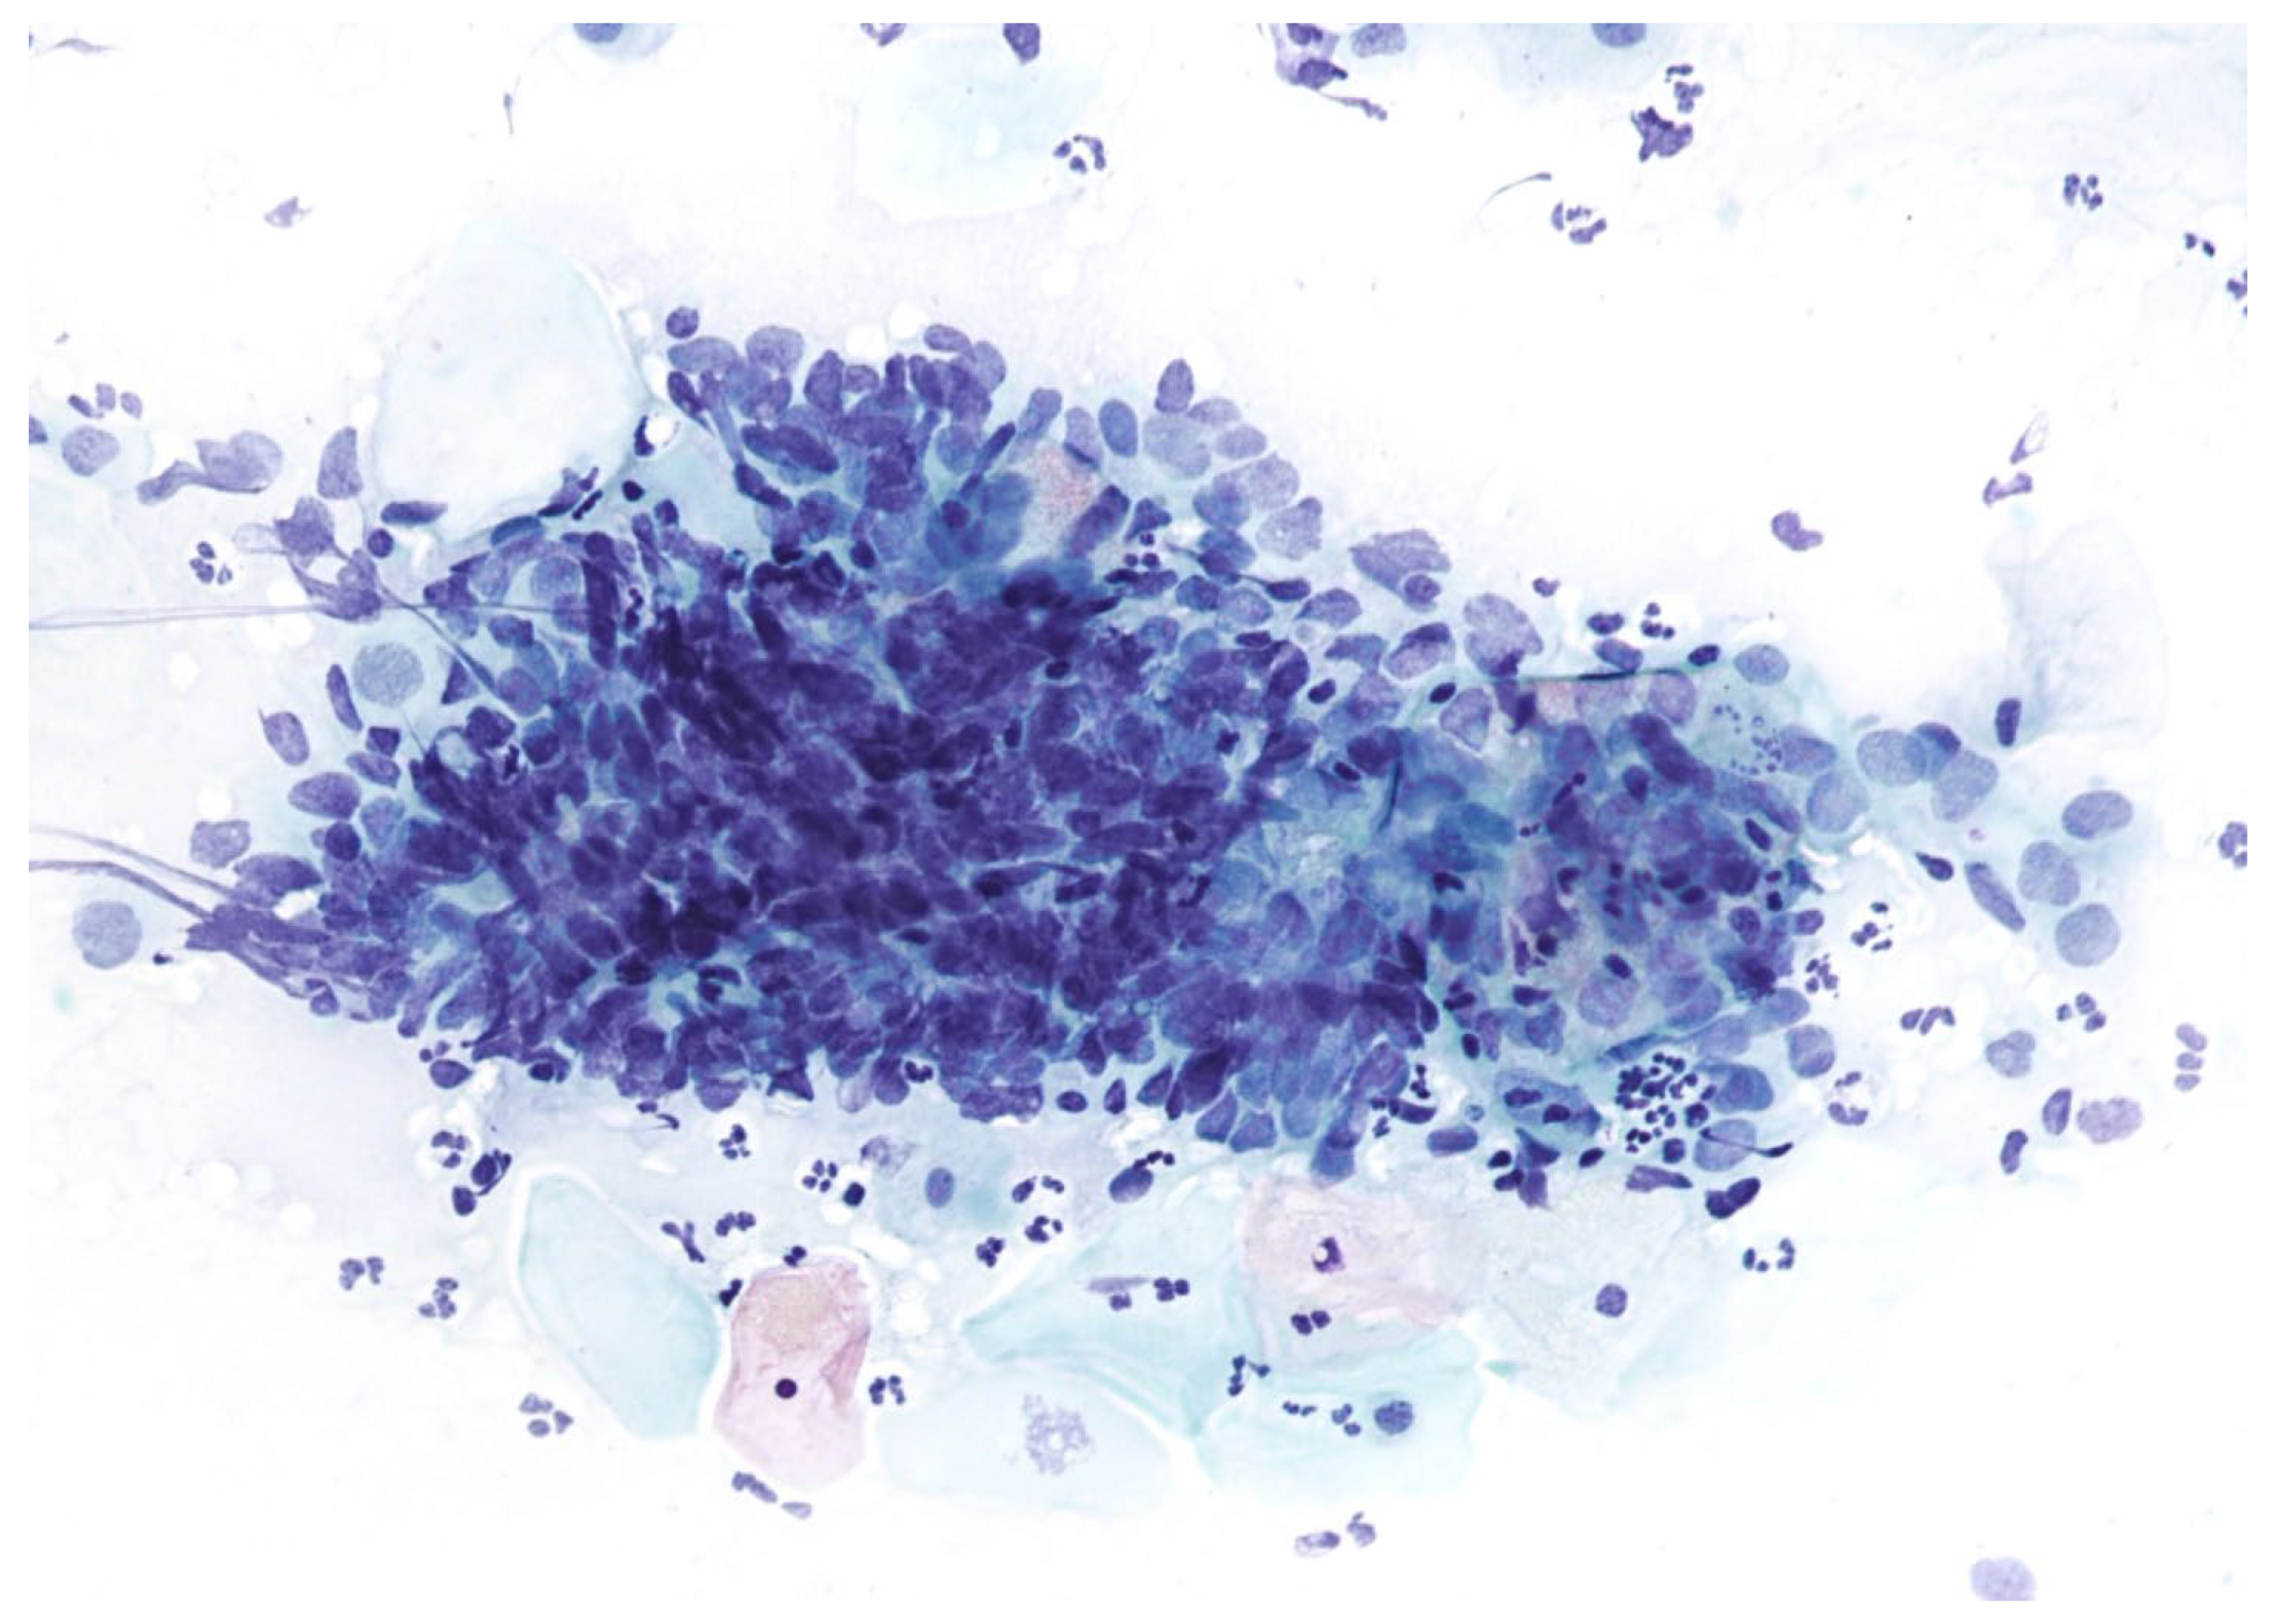

4. Molecular Biology of Cervical Precancerous Lesions and Cervical Cancer

5. The Rationale and Use of p16/Ki67 Dual Staining in Cervical Cancer Screening